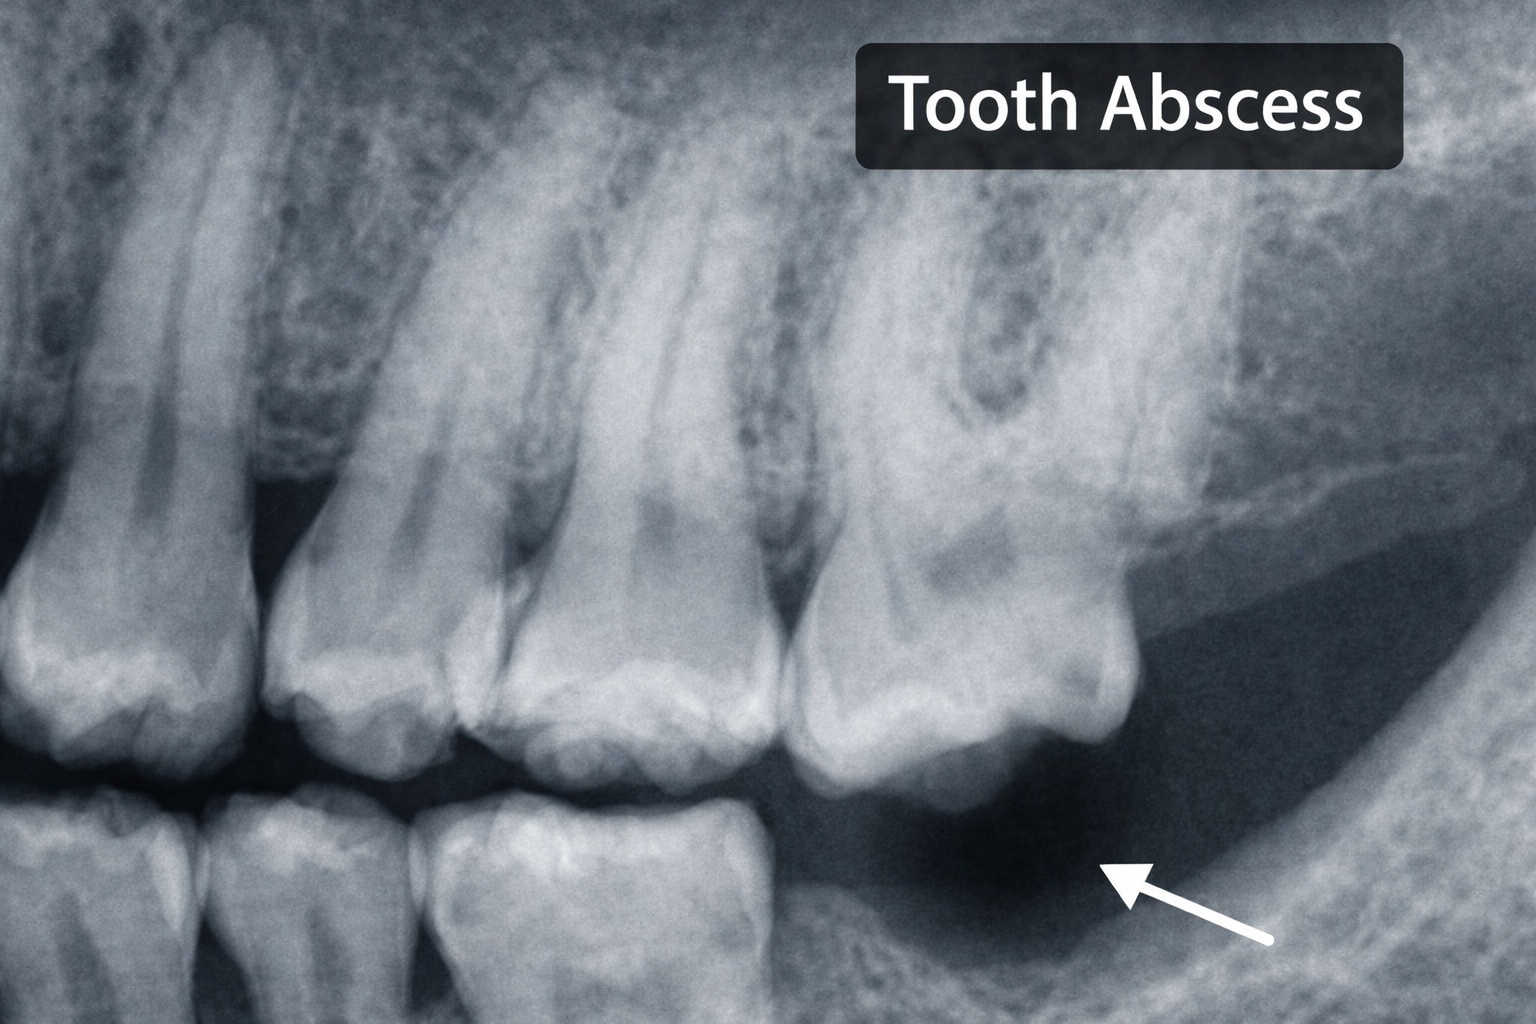

A dental or tooth abscess is a collection of pus caused by bacteria, usually triggered by untreated decay, a cracked tooth, or advanced periodontal disease. The infection can occur:

- Periapically – at the tip of the root after the pulp has become necrotic.

- Periodontally – along the side of the root, linked to deep periodontal pockets.

Either way, bacteria enter spaces they should never reach. The body responds with inflammation, fluid and pus, which build up pressure inside bone and soft tissue. That pressure is what creates the intense, throbbing pain many patients describe.

Clinicians will of course confirm the diagnosis with history, clinical exam, and radiographs. For patient education material in your practice, many dentists link to resources from the Australian Dental Association.

Stage 3 – Localised tooth abscess

A true abscess forms as pus collects in bone or soft tissue. Pain is usually constant and severe. Swelling may be visible intraorally or extraorally. A sinus tract may develop, giving temporary relief when it drains.